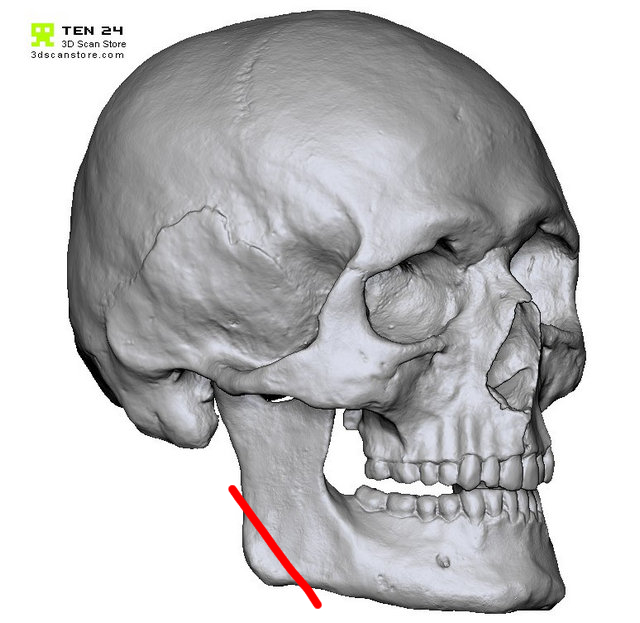

... why not going for a cut like below to fix so-called "inward gonions" ? You can then imagine a variety of movements and segmentations to attain the desired result, akin to chin osteotomy.

... why not going for a cut like below to fix so-called "inward gonions" ? You can then imagine a variety of movements and segmentations to attain the desired result, akin to chin osteotomy.